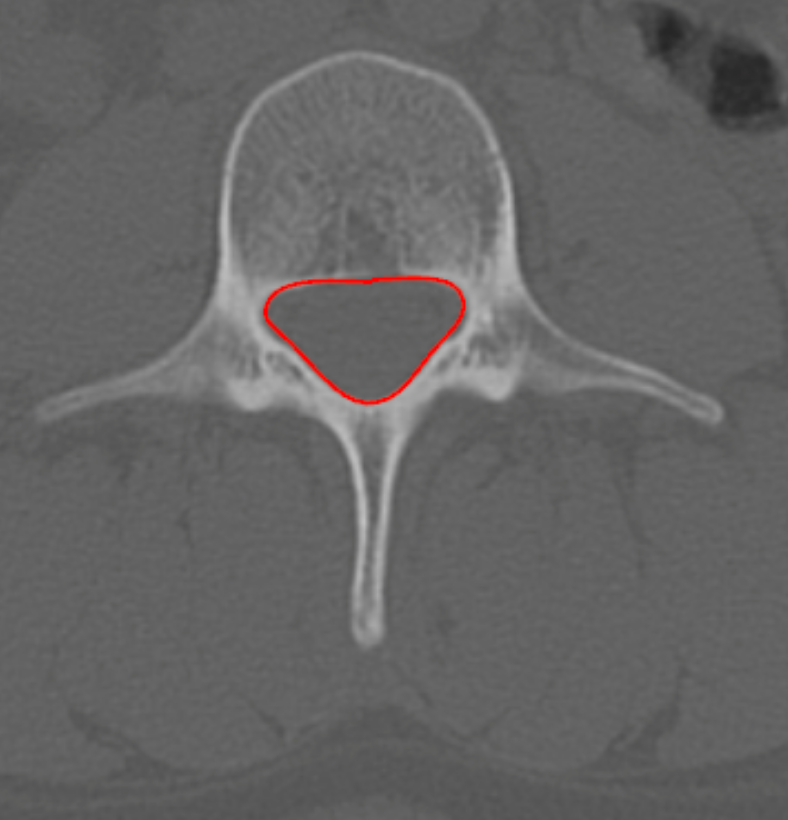

Cross-Sectional Area of Canal (CSA)

Lumbar spinal canal CSA on CT quantifies the bony cross-sectional area available for the thecal sac and cauda equina. It is a robust morphologic parameter for diagnosing lumbar spinal stenosis, particularly useful when MRI is contraindicated or to characterize osseous encroachment from facet hypertrophy, laminar thickening, or congenital canal narrowing.

• Using a freehand or polygon ROI tool, trace the inner cortical margin of the bony spinal canal, including the laminae, pedicles, and posterior vertebral body margin.

• Close the ROI to compute the cross-sectional area (mm²).

3) Normal vs. Pathologic Ranges

• Normal CSA: > 120 mm2

• Borderline narrowing: 100 - 120 mm2

• Lumbar spine stenosis: < 100 mm2

• Severe stenosis: < 75 mm2

• Critical stenosis: < 50 mm2

CT-based CSA primarily reflects bony stenosis; it does not account for ligamentum flavum or disc material — correlate with MRI dural sac CSA for neural compromise.